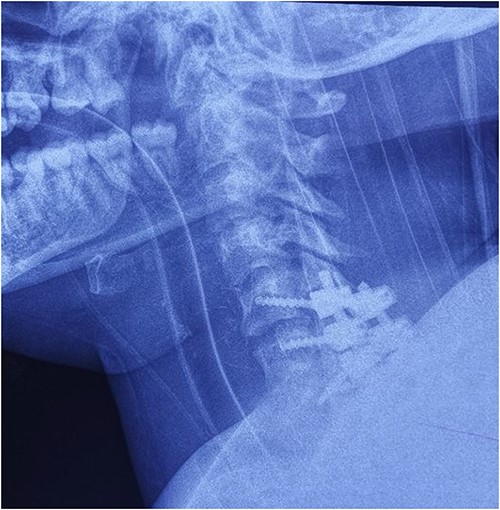

On the fourth day after the injury, the patient was conscious, on low doses of vasopressor support. What was surprising was that in her conscious state she had weakened abduction of the left shoulder, while the right arm and legs were completely plegic (ASIA A). We decided to perform posterior reduction and stabilization from the level of C5 to T1 (Figs 3–5). On the first postoperative day, a follow-up X-ray of the cervical spine was performed (Figs 6 and 7).

Intraoperative finding after repositioning and stabilization: screws placed into the C5-C7 massae laterales and the T1 pedicles; fixation performed with titanium rods.

Cervical spine X-ray postoperatively – AP view: properly positioned osteosynthesis material.

Cervical spine X-ray postoperatively – lateral view: properly positioned osteosynthesis material.